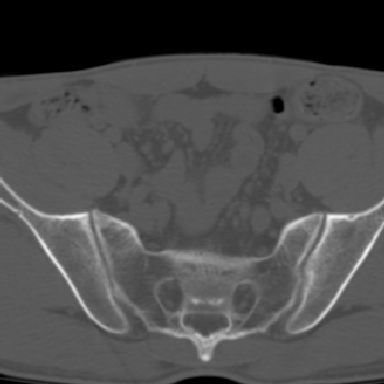

m 30 腰背部不适半年; 清晨时僵硬; 活动症状有所改善

双侧骶髂关节下2/3关节面模糊,毛糙,可见小囊状骨质破坏区.支持强直性脊柱炎.

强直性脊柱炎的早期改变!不仅表现为双侧骶髂关节,第5腰椎与骶椎间的关节突关节也有类似改变。

双侧骶髂关节下2/3关节面模糊,毛糙,髂骨侧可见小囊状骨质破坏区,骶髂关节间隙增宽(软骨破坏期)。支持早期强直性脊柱炎。

双侧骶髂关节下2/3关节面模糊、毛糙,可见小囊状骨质破坏区,呈虫咬状改变,周围可见增生硬化.支持强直性脊柱炎早期表现.

双侧骶髂关节髂骨面硬化,毛糙,小囊变,属于早期强直性脊柱炎